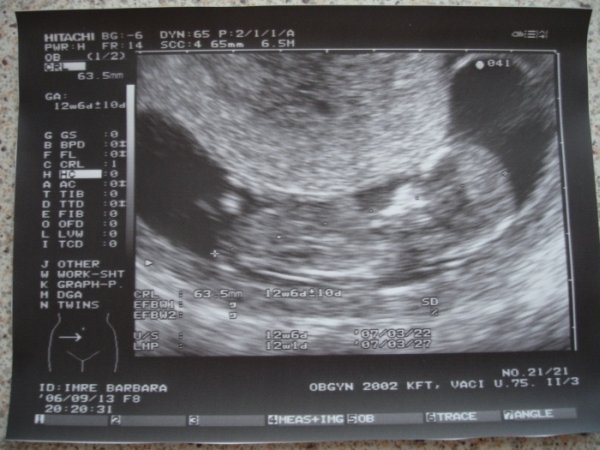

Picúr 12 hetes

Pocakfotó 13+5